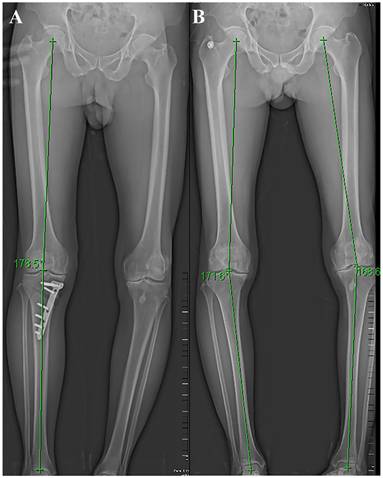

Preoperative evaluation includes clinical evaluation and imaging evaluation. Clinical evaluation mainly focuses on the collection of their medical history, physical examination, clinical symptoms, etc. Focus on the precise area of the patient's pain, factors that worsen the pain, and whether there is joint locking or instability. The patella, meniscus, and ligaments should also be evaluated. Patients with the following symptoms are not suitable for surgery: pain that is not consistent with the lesion site, symptomatic patellofemoral degeneration, and severe damage to the meniscus or ligaments. Imaging evaluation was mainly achieved by full-length radiographs of the lower limb, along with front and lateral radiographs of the knee joint (Figure 1). Surgeons use preoperative X-rays to accurately evaluate the lower limb force line (Mikulicz line) and the angle that needs to be corrected [39]. CT scanning can better display bone structure, and MRI scanning can better observe the condition of the meniscus, ligaments, and cartilage. Accurate preoperative imaging examination is crucial for evaluating the patient's condition, determining surgical indications, and selecting surgical methods.

Figure 1

Postoperative (A) and preoperative (B) lower limb X-ray and force line.

Int J Med Sci Image